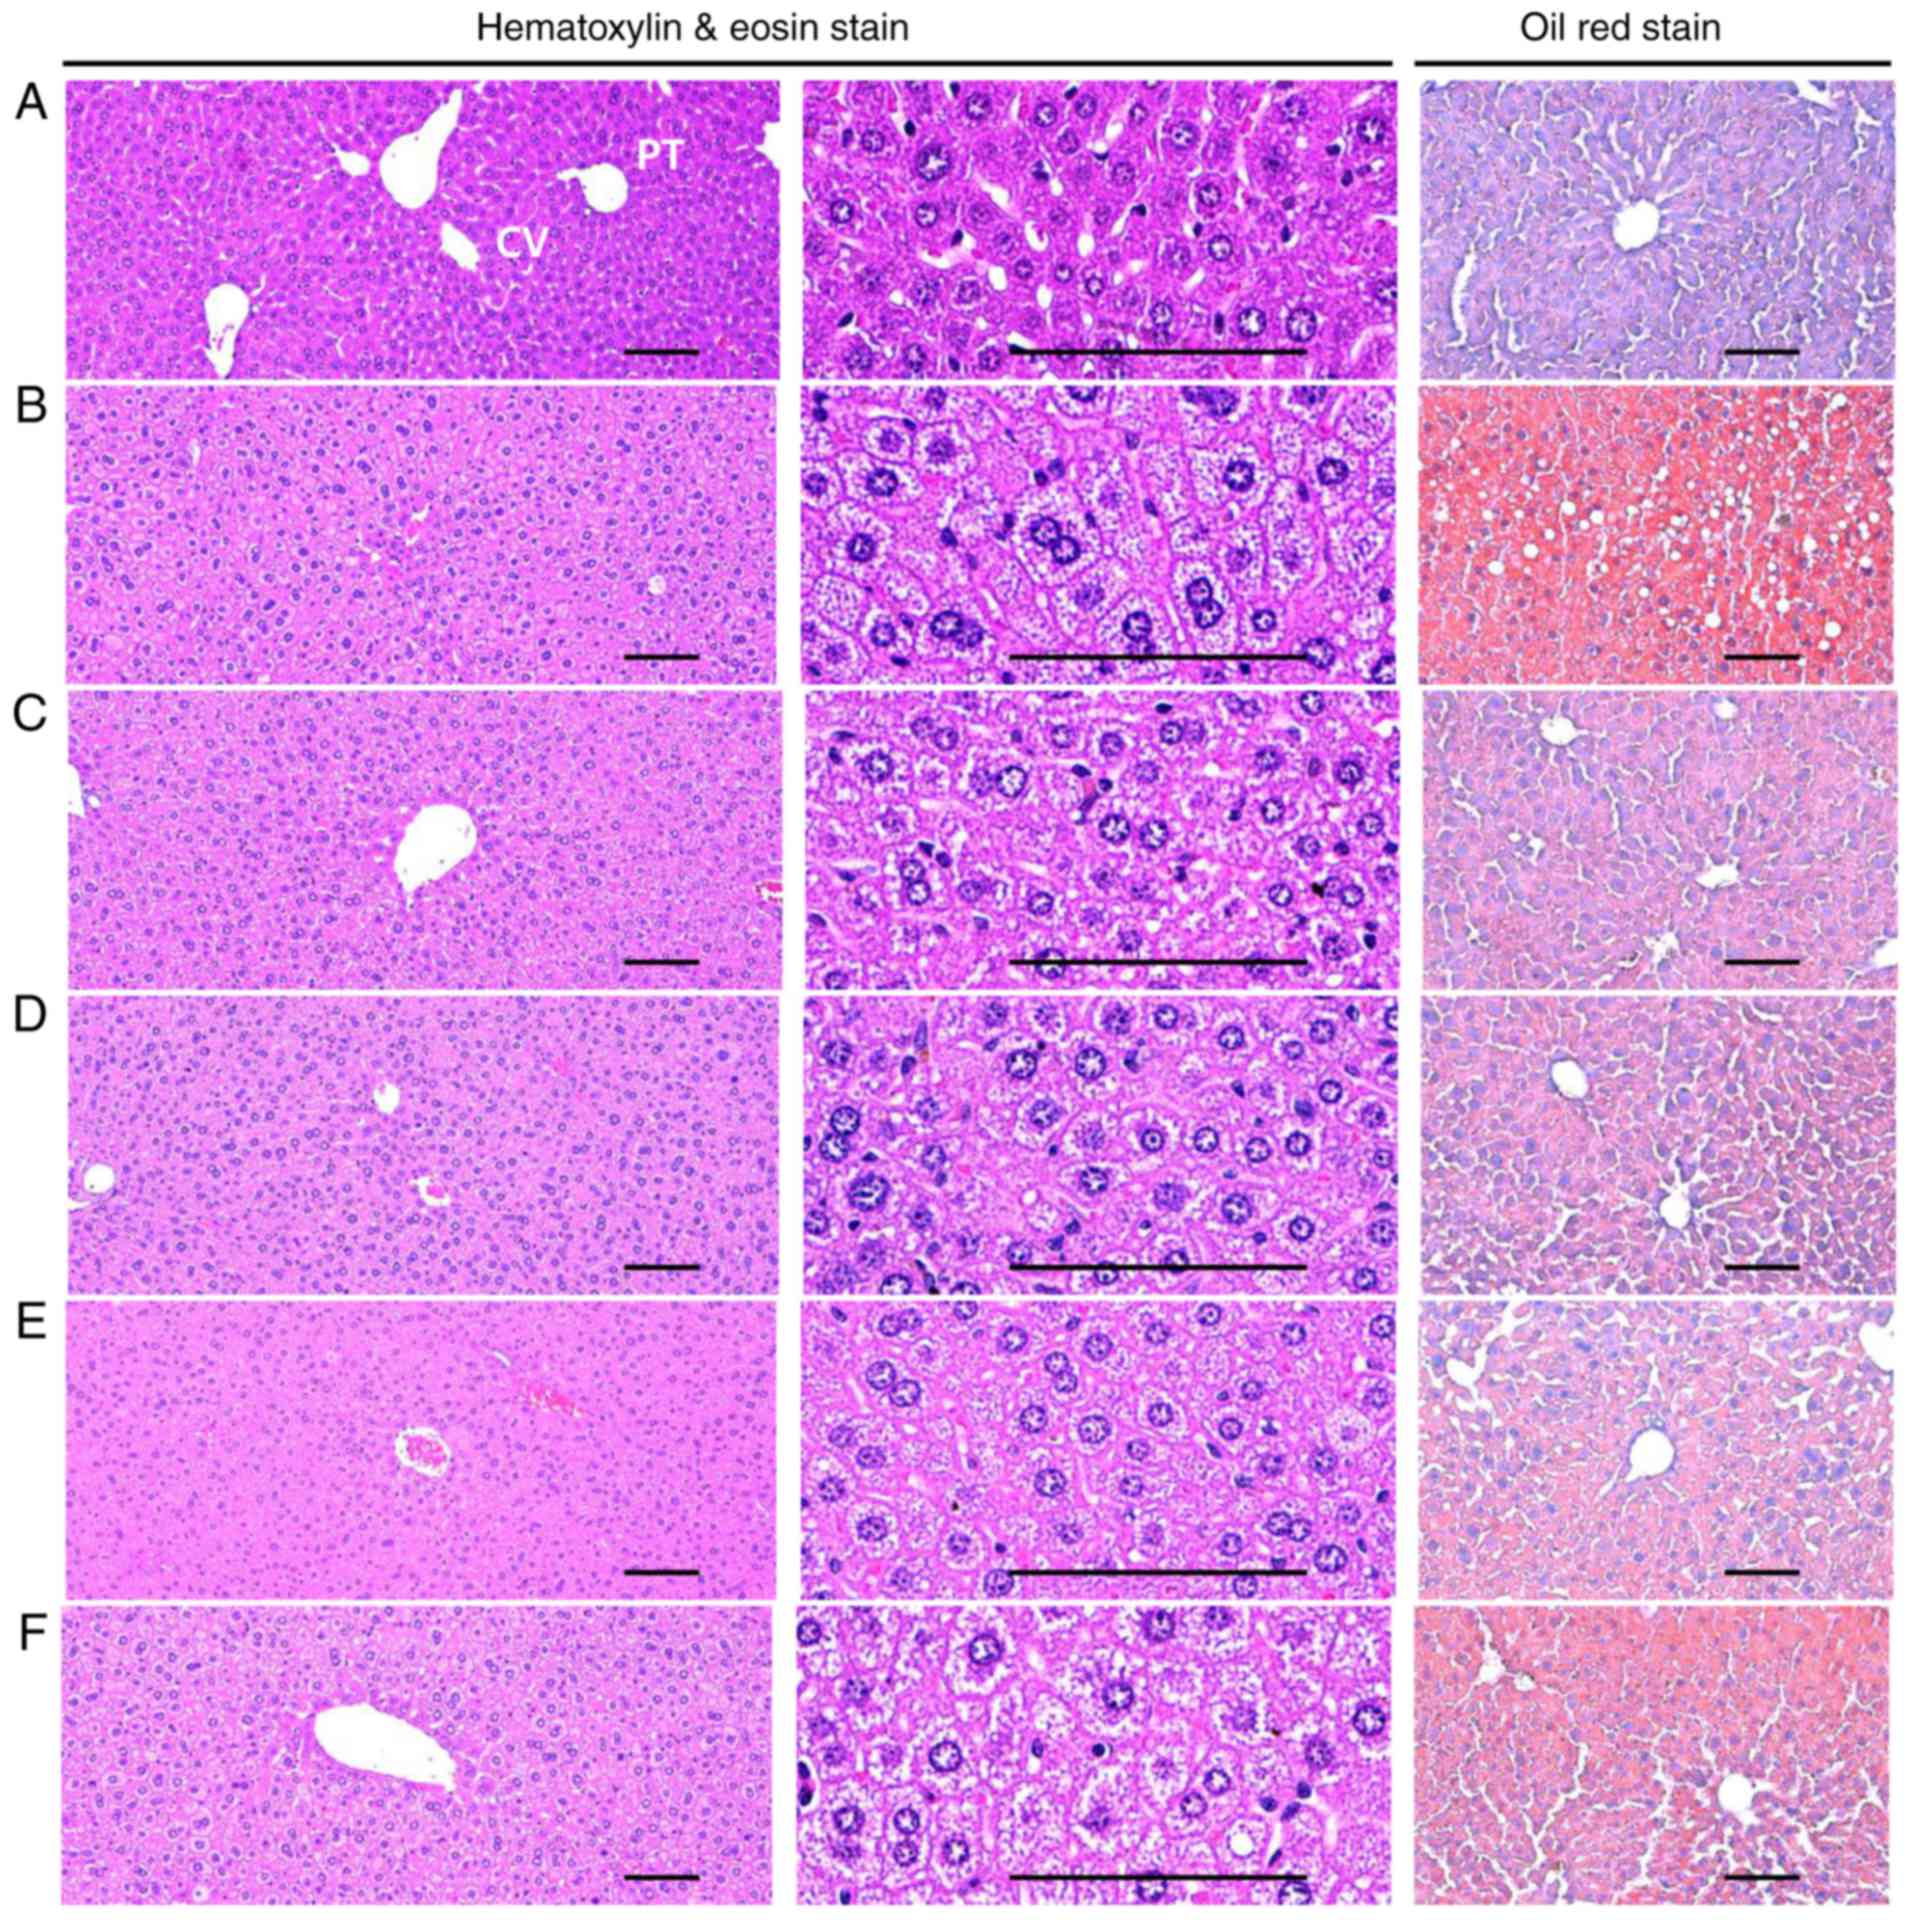

Effects on hepatocyte hypertrophy and

steatohepatitis

A significant (P<0.05) increase in the mean

diameter of the hepatocytes (hypertrophy) was observed in the HFD

control groups compared with in the healthy control group. However,

hypertrophy was markedly decreased in all treatment groups compared

with in the HFD control mice. Specifically, all BHe-treated mice

exhibited clear dose−dependent decreases in the hepatocyte

hypertrophies, the mean hepatocyte diameter, compared with in the

HFD control groups (Table

VIII; Fig. 7). A significant

increase of 156.79% in the mean diameter of hepatocytes in the HFD

control group was observed, with changes of −33.99, −20.38, −29.91

and −33.80% in the metformin (250 mg/kg) and BHe (400, 200 and 100

mg/kg)-treated groups, respectively.

A significant (P<0.05) increase in

steatohepatitis (proportion of regions with fatty change in the

liver parenchyma) was also observed in the HFD control group

compared with in the healthy control group. However, the changes

were decreased to the level in the healthy control group by all the

test treatments. Specifically, all BHe-treated mice exhibited

dose-dependent decreases in the steatohepatitis area compared with

in the HFD control group (Table

VIII; Fig. 7). The

steatohepatitis area was increased by 995.16% in the HFD control

group, with changes of −42.09, −23.48, −32.74 and −45.62% in the

metformin (250 mg/kg) and BHe (400, 200 and 100 mg/kg)-treated

groups, respectively.